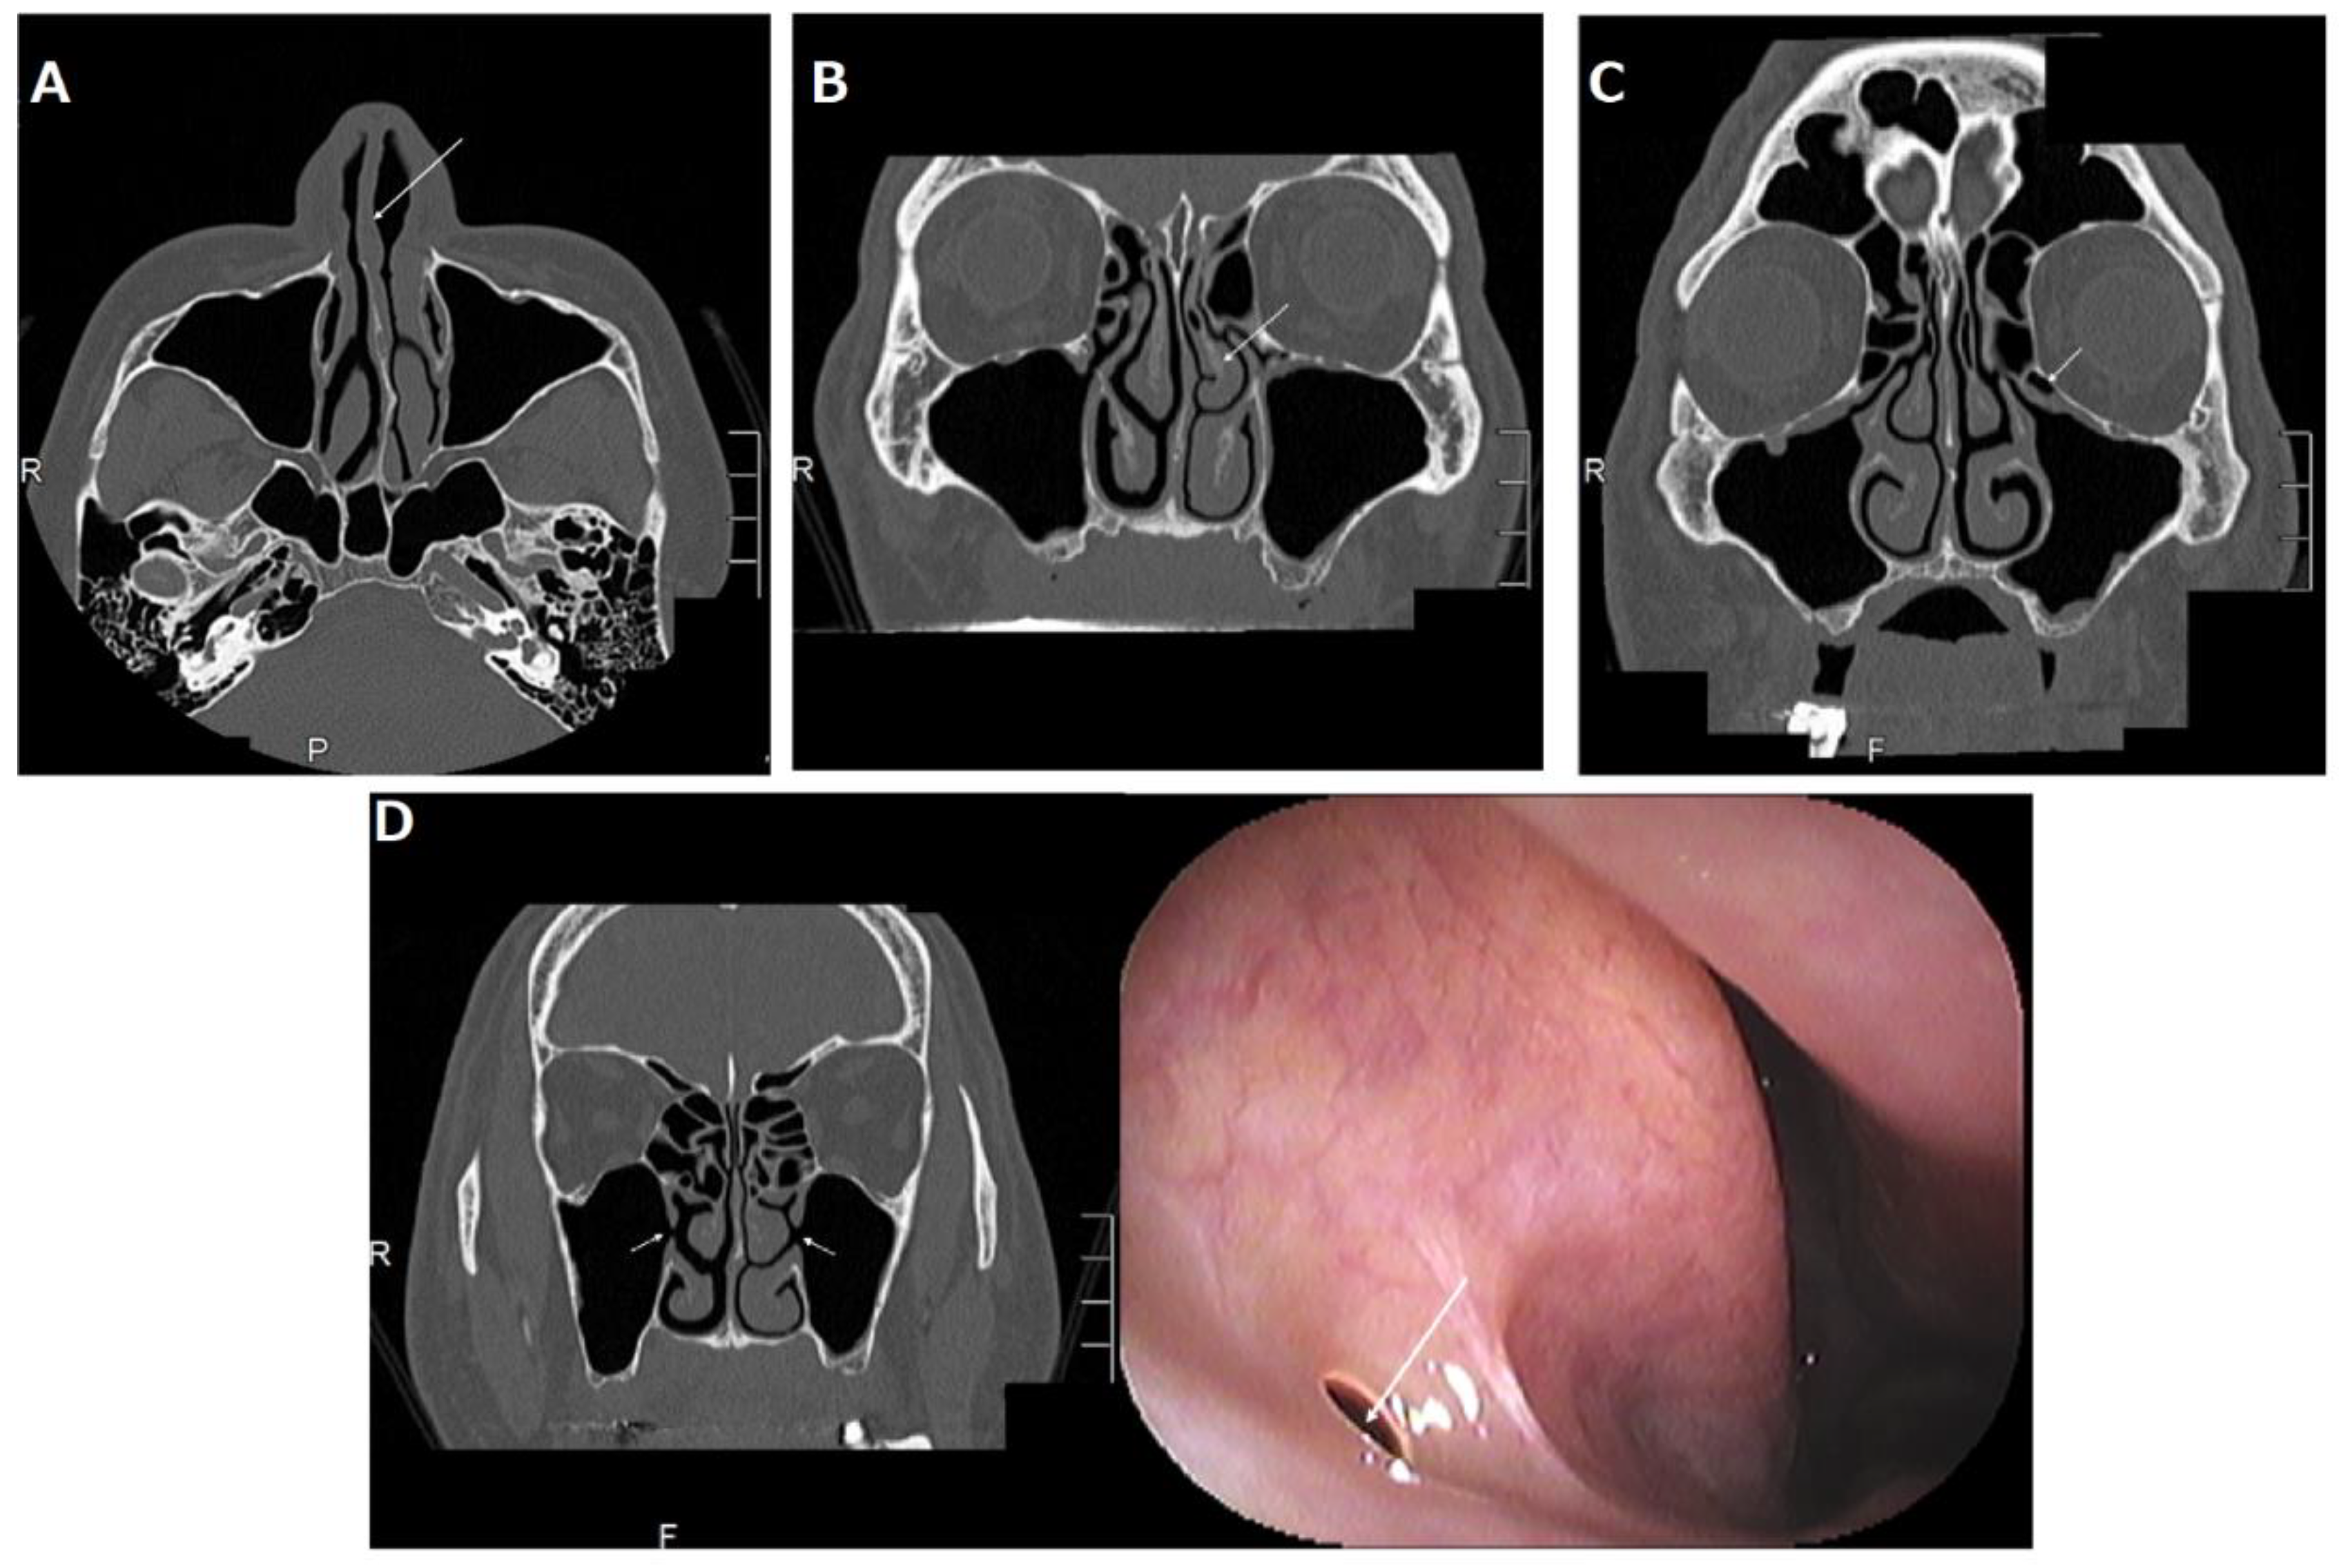

Figure 4.

(A) Right nasal septal deviation (arrow); (B) left paradoxical middle turbinate (arrow) and left concha bullosa of the middle turbinate; (C) left Haller cell (arrow); (D) bilateral accessory ostium of the maxillary sinus (arrow in CT (left panel)) and right accessory ostium (arrow in nasal endoscopic examination (right panel)). This was originally published in Case Reports in Otolaryngology: Suzuki-Yamazaki, M.; Takahashi, K.; Takada, S.; Kato, Y.; Baba, Y. “A successful treatment regimen for the prevention of sinusitis after maxillary sinus floor elevation surgery in a high-risk case.” Case Rep. Otolaryngol. 2020, 2020, 6869805 [16].

A systematic review indicated that a deviated nasal septum is associated with an increased prevalence of rhinosinusitis [11] because the curvature of the convexness of the nasal septum laterally displaces the middle turbinate and uncinated process, narrowing the ethmoidal infundibulum and reducing the ventilation and drainage of the maxillary sinus (Figure 4A).

Fadda et al. showed that anatomical variations in the middle turbinate, such as the concha bullosa and paradoxical middle turbinate, are associated with an increased prevalence of rhinosinusitis [12] because they laterally displace the uncinated process, narrowing the ethmoidal infundibulum and reducing ventilation and drainage of the maxillary sinus (Figure 4B).

2.3.3. Haller Cells

Haller cells are defined as infraorbital ethmoid cells. Haller cells also cause rhinosinusitis [12] because the presence of Haller cells can induce the stenosis of the ethmoidal infundibulum, consequently reducing the ventilation and drainage of the maxillary sinus (Figure 4C).

2.3.4. Accessory Ostium

The accessory ostium is located behind the maxillary natural ostium. Doctors should be careful not to confuse it with a natural ostium on computed tomography (CT) (left panel in Figure 4D). The natural ostium cannot be confirmed by nasal endoscopy, but the accessory ostium can be confirmed by endoscopy (right panel of Figure 4D). Although some doctors think that the accessory ostium might improve drainage of the maxillary sinus, it may pose a risk for maxillary sinusitis, because the presence of an accessory ostium can lead to chronic maxillary sinusitis by recirculation of mucus secretions, as well as a decrease in the drainage function of the maxillary sinus [13].